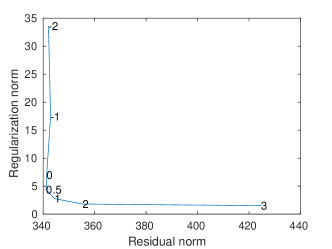

A regularization parameter common to all the PC components is chosen by inspecting the plot of the regularity of the first PC covariance functions () versus the residual norm, for different choices of the parameter. This is a version of the L-curve plot (Hansen, 2000) and is shown on the left panel of Figure B.2. Here we show the results for , in the appendices we show the results for . The energy maps of the estimated , and resulting from the analysis are shown in Figure 11. These are associated with the first three PC covariance functions , and . High intensity areas, in yellow, indicate which areas present high average interconnectivity, either by means of positive or negative correlation in time.

In Figure B.2 we show the L-curve plots associated with the PC covariance models applied to the dynamic and multi-subject functional connectivity studies.